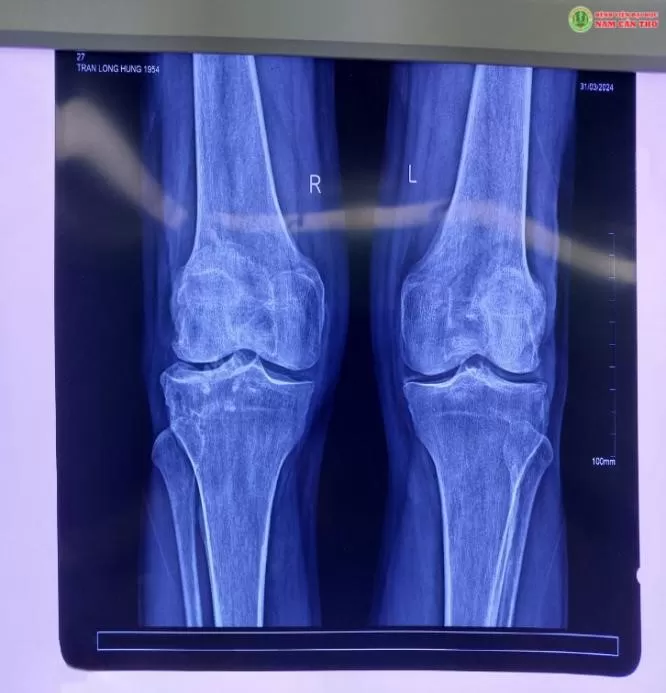

Qua khám lâm sàng và kiểm tra các xét nghiệm hình ảnh, bệnh nhân được chẩn đoán thoái hóa khớp gối, khai thác tiền sử bệnh, theo dõi hồ sơ bệnh án, đội ngũ y bác sĩ Khoa ngoại tổng hợp đã tiến hành hội chẩn và quyết định thống nhất phẫu thuật nội soi, cắt lọc.

Kết quả nội soi phát hiện bệnh nhân bị sụn xương thoái hóa (giống sỏi) do thoái hóa khớp gối và canxi hóa tạo thành gai xương lâu năm khiến bệnh nhân đau, gặp khó khăn trong vận động.